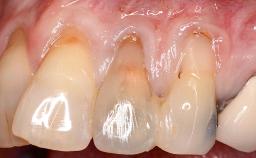

It is sometimes necessary to remove and replace compromised implants. This case is a clear example of the need for multiple steps to achieve an optimal therapeutic result for patients with non-salvageable implants. It illustrates how the lost soft and hard tissues were rebuilt in a sequence that improved the healing of the hard tissues and assured their long-term stability. The 35-year-old healthy patient presented with clinical attachment loss on the proximal and lingual surfaces of the natural dentition. Some gingival recession was present on natural teeth, particularly in the posterior sextants (S1, S3, S4, and S6).